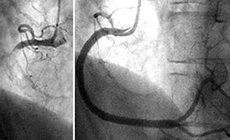

狭心症、心筋梗塞、末梢動脈疾患が疑われる患者さまがいらっしゃいましたら、循環器内科外来あてにご紹介ください。

循環器専門の医師が患者さまを診察し、適切な検査計画を検討させていただきます。